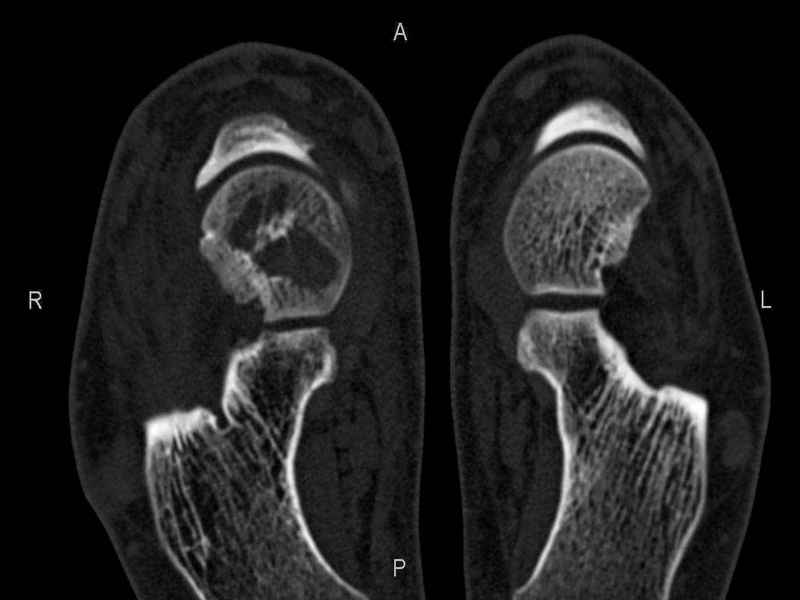

На СКТ картина рассекающего остеохондрита блока

таранной кости, киста шейки таранной кости с признаками импрессии суставной поверхности. А

также - разрастания переднего края б\берцовой кости сопровождающиеся клиникой импиджмент

синдрома.